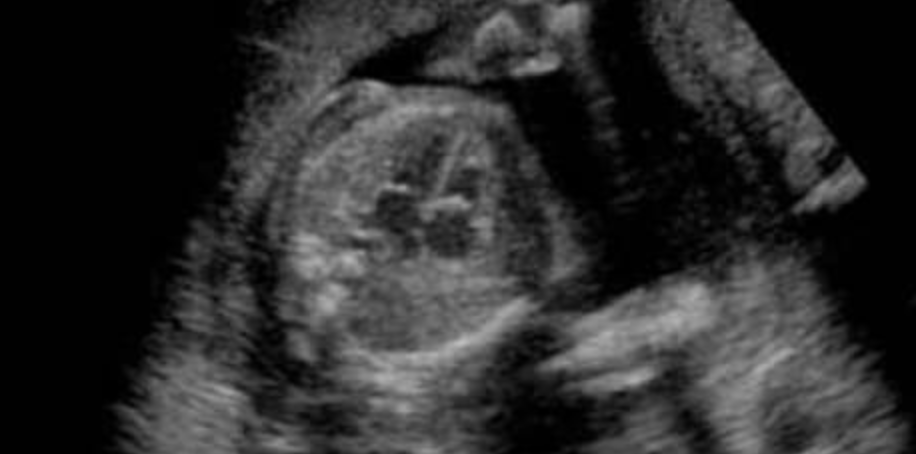

ATLANTA – Atlanta Democrat Stacey Abrams earlier this week made a bold statement regarding when the heartbeat of a baby begins.

In the following video, Abrams said that the heartbeat of a six week old child in the womb was not real but was manufactured: